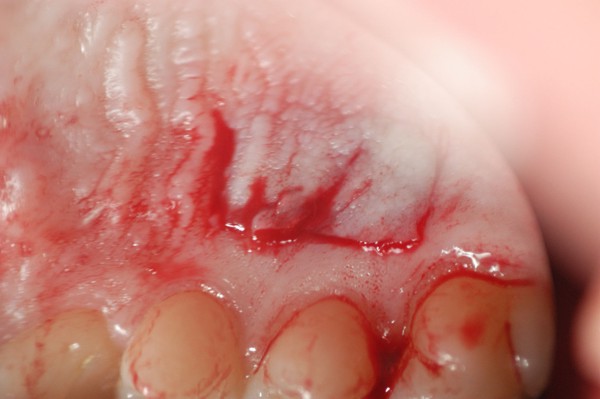

Este artículo pertenece a la categoría: Casos Clínicos

Abstract: Las fuerzas anterógradas traumáticas son en general las causantes de fracturas radiculares en el sector anterior de la boca. Desarrollo: El paciente se presenta a la consulta , con la fractura de una funda de porcelana inyectada en la zona cérvico palatina, solicitando simplemente la reparación en boca para evitar rozamientos linguales. Dicha funda con un perno colado en oro y su correspondiente endodoncia, habían sido realizadas en mi clínica varios años atrás, con un «aparente éxito total». Radiograficamente, se encuentra una fractura radicular cercana al tercio gingival Observada la oclusión de las piezas anteriores, podemos ver que el vínculo ideal de Acoplamiento, no se cumple, habiendo una relación de franco contacto la que ha provocado la fractura. Llevando al paciente a Oclusión en Relación Céntrica, podemos ver el espacio a nivel anterior, correspondiente a la centricidad mandibular. En esa misma posición , es dable percibir una faceta parafuncional mesial del primer premolar superior… …que antagoniza con una faceta parafuncional distal del canino inferior… ..constituyendo un plano inclinado que provoca la antelación mandibular o Discrepancia Horizontal, fracturando la raiz del incisivo central. Extraida la porción coronal de la raiz, pensamos en la realización de un Implante Inmediato, a pesar de la presencia de una fístula dado que se trataba de un central, decisión que obtuvo éxito implantario mas no estético, según veremos luego. Era fundamental conservar lo mas posible las tablas óseas, que de hecho había perdido la porción cervical Realizamos una incisión que conservara las papilas de las piezas adyacentes. Realizamos la exodoncia mediante un instrumento construido «ad hoc» que denomino: Con lo que obtenemos la preservación «ad integrum» de las corticales peridentarias remanentes. Instalamos entonces un implante T.B.R. de 15 mm de largo por 4 mm de diam. con cuello de zirconio de 3,5 mm …quedando tres espiras sin hueso por vestibular, producto de la tabla perdida, Incidimos el periostio a nivel apical del colgajo para obtener mayor paño quirúrgico, y legramos un bolsillo palatino sin incisiones de descarga, para la inserción de la membrana. Suplementamos la carencia ósea vestibular con «BIOSS» …e instalamos una membrana reabsorbible «BIOGUIDE» , que fijamos con el mismo implante, y calzamos por palatino. Suturamos Instalamos nuestra provisional previamente confeccionada, sobre un abuttment de titanio. Y controlamos radiograficamente Pasadas tres semanas del retiro de los puntos, observamos una cicatrización alta que nos muestra el anillo de zirconio del implante. ……………………………………………….. Transcurridos tres meses preparamos una nueva cirugía, dirigida a instalar un injerto autólogo de conectivo en el área del anillo, con un nuevo desplazamiento del colgajo vestibular. Tomamos tejido conectivo del paladar a nivel de los premolares, mediante una incisión mucosa «en libro», y disección del conectivo subyacente. Lo posicionamos en vestibular del anillo de zirconio y lo fijamos mediante sutura Y semanas después nos encontramos con un nuevo fracaso de orden estético. ……………………………………………….. En la actualidad, el caso esta estable , aún con su funda provisional, a la espera de un nuevo intento plástico, mediante Injerto Libre de Encia. ………………………………………………….. ESQUEMA MECÁNICO DEL FENÓMENO …que además de los hechos mostrados en el caso presentado, frecuentemente provocan en el sentido antero posterior los fenómenos de DISPERSIÓN ,en el maxilar superior…y de APIÑAMIENTO en el maxilar inferior. CONCLUSIONES: Además del rigor académico que nos convoca… esta; nuestra casa…nos otorga la confianza que solo da el saber que estamos siempre entre amigos, que cada vez son más. Por tanto es que debo decir: YO fui el responsable de dicha fractura… …porque… …..que hubiera sucedido si hubiera hecho todo el trabajo implantario sin ajustar previamente su oclusión? Seguramente a esta altura del caso…también hubiera fracasado el implante. Siempre decimos que se aprende de los errores más que de los aciertos, y Dr. Carlos A. Acuña Priano

Fig.28(Pie de foto: Incisión mucosa)

Fig.29(Pie de foto: Levantamiento de colgajo superficial)

Fig 30(Pie de foto: Disección del conectivo)

Fig 31:(Pie de foto.:Pieza obtenida in vitro)